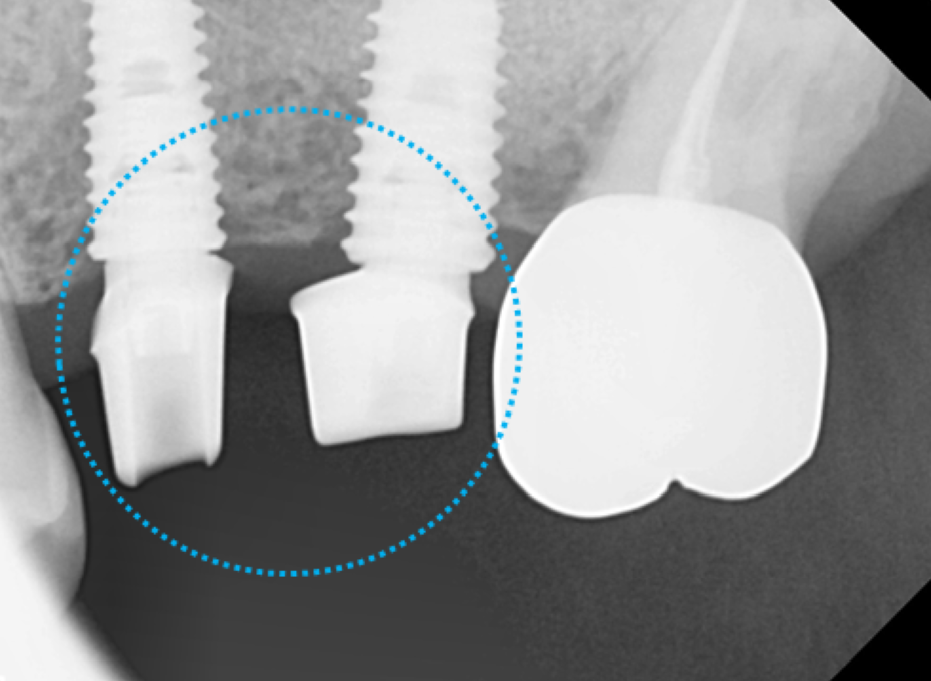

본뜨는 나사를 연결해서 인상을 채득하면,

이렇게 기공소에서 맞춤 어버트먼트로 제작이됩니다.

확대해서 보는 치근단 엑스레이 보시면,

하얗게 뿌리부분에 신경치료 재료가 잘 들어가

잘 마무리 된 것을 볼 수 있습니다.

기공소에서 맞춤 지대주가 제작되어 나왔습니다.

뼈 상태에 따라 임플란트의 위치가 조금 달라진 경우에는,

이렇게 맞춤 지대주의 방향을 바꿔서 각도를 조절합니다.